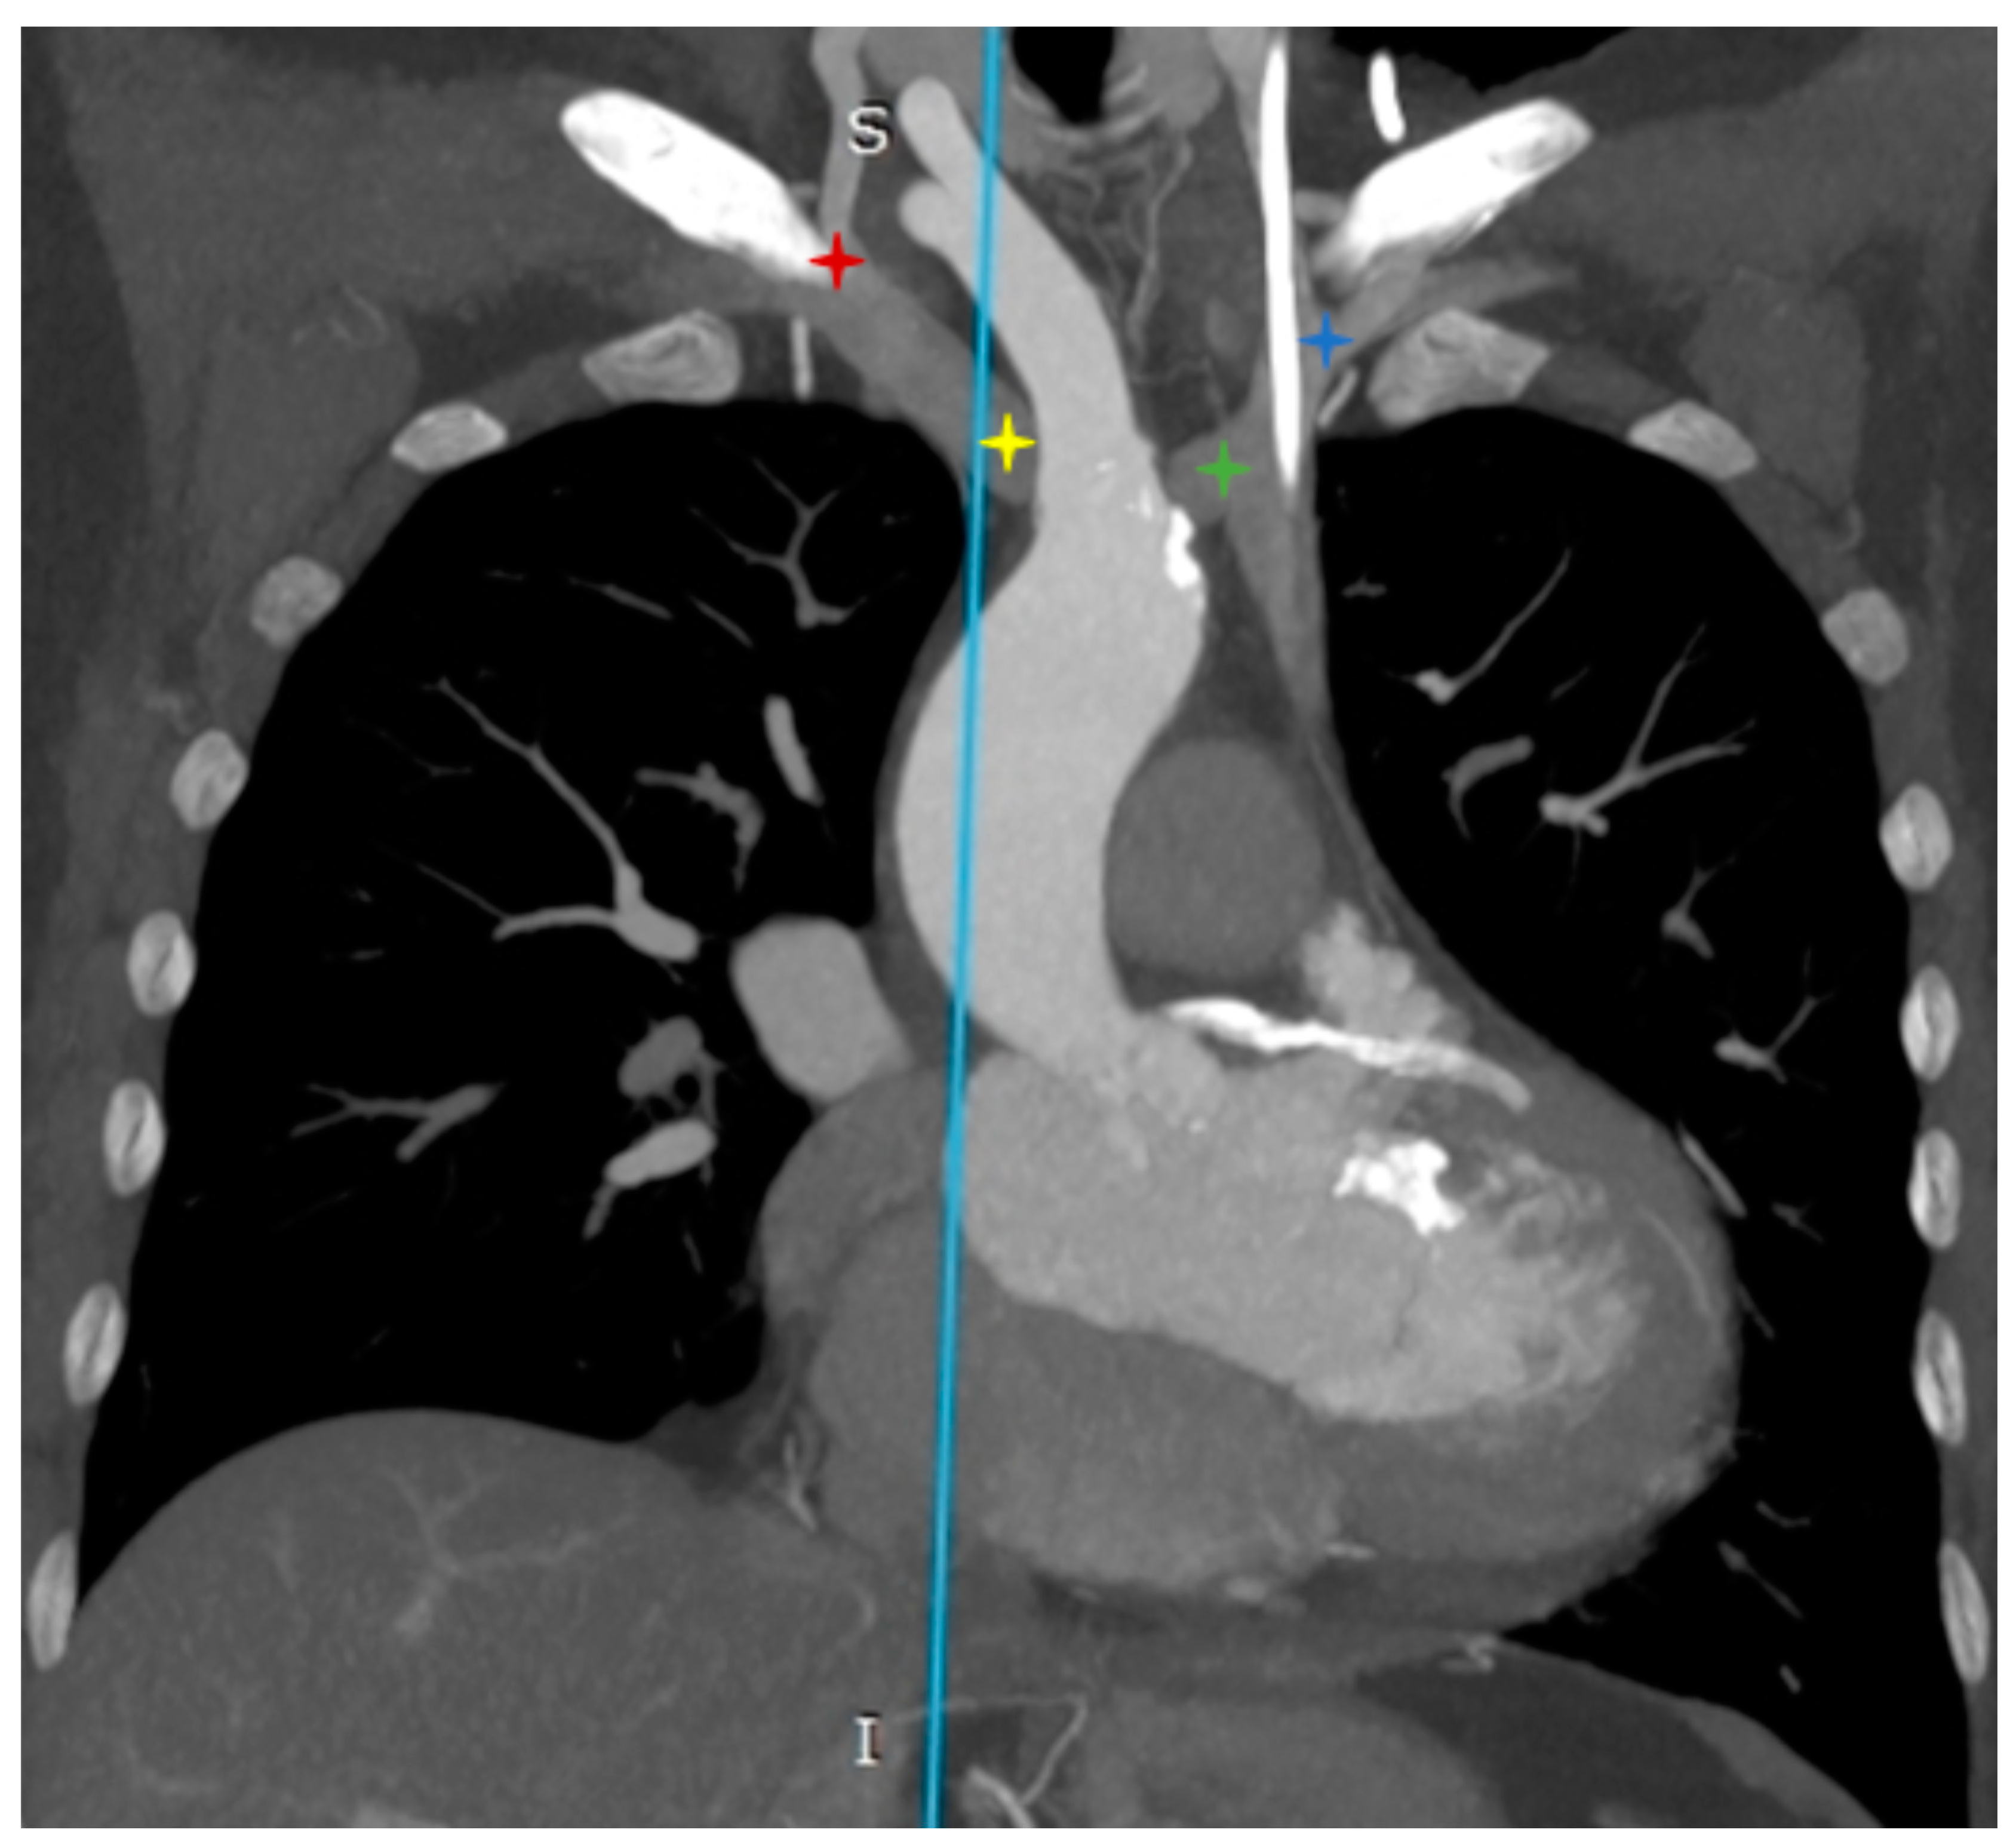

- Incidental vascular finding No. 1: Persistent Left Superior Vena Cava with Absent Right Superior Vena Cava.